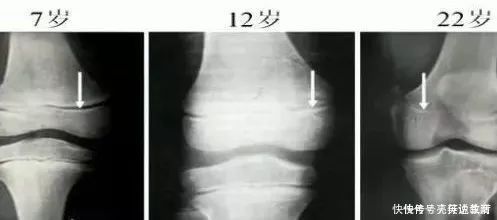

事实上,孩子想要长成大高个,抓住“生长要素”是关键很多父母应该都知道,孩子身高在停止生长之前,都会有一个非常明确的信号,就是“骨骺线闭合”。

而骨骺线,就是孩子长成大高个最为关键的生长要素。

所谓骨骺线,是人体骨骺和干骺端的软骨,随着孩子的成长,这条在X光片下呈现投名状的骨骺线,会越来越窄,直至闭合,孩子骨骼停止发育。

在一般情况下,男孩子骨骺线在17岁左右就会闭合,而女孩子在15岁左右就已经会闭合。